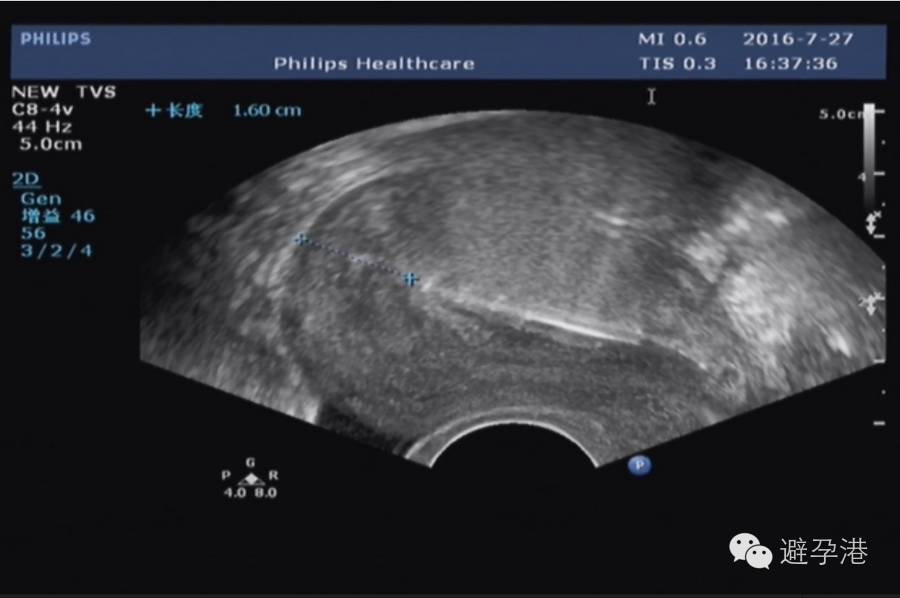

1.纵切面:在宫内可显示出串珠状六个亮点的强回声带。

吉妮致美环怎么样吉妮致美节育器超声图像解读_https://www.jmylbn.com_新闻资讯_第2张

吉妮致美环怎么样吉妮致美节育器超声图像解读_https://www.jmylbn.com_新闻资讯_第3张